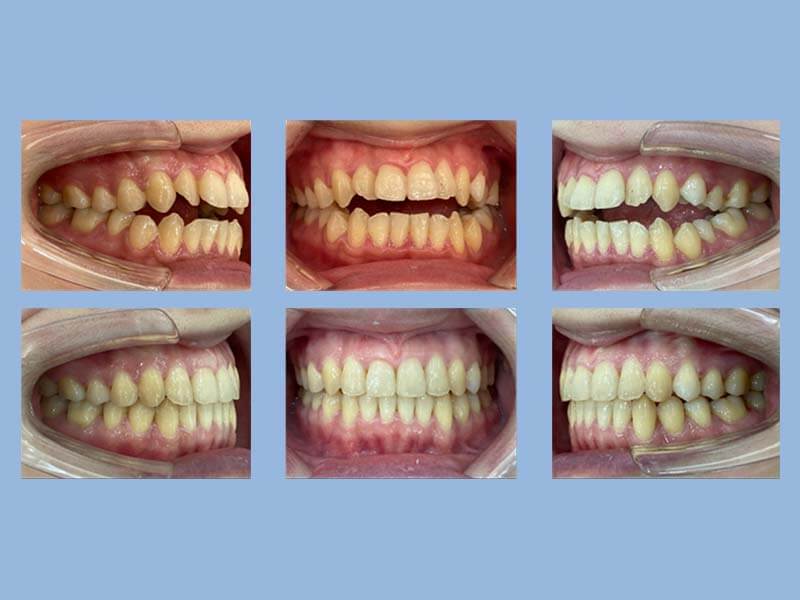

湯先生 (21歲) 矯正完成

狀態 : 牙齒暴和擁擠、沒拔牙